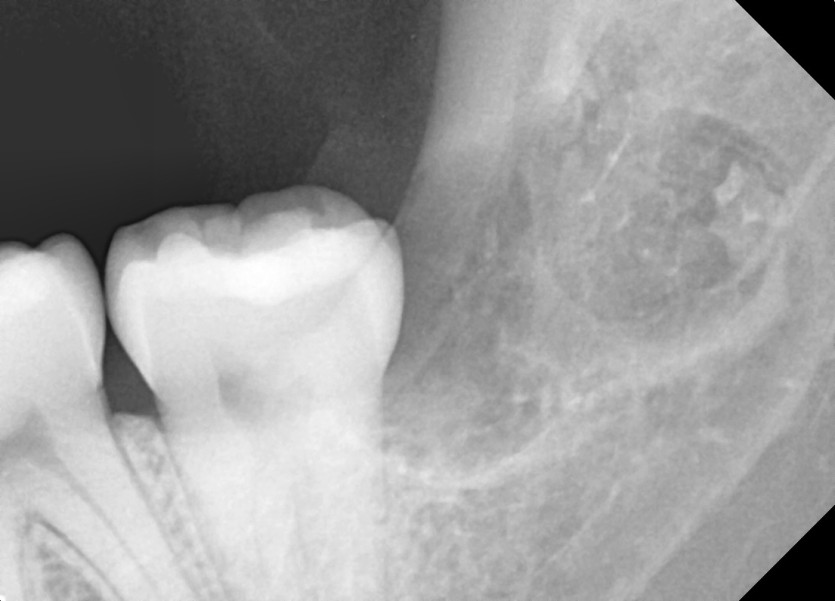

#28,38 사랑니 발치

구강 외과 전문의가 당일 발치했습니다.